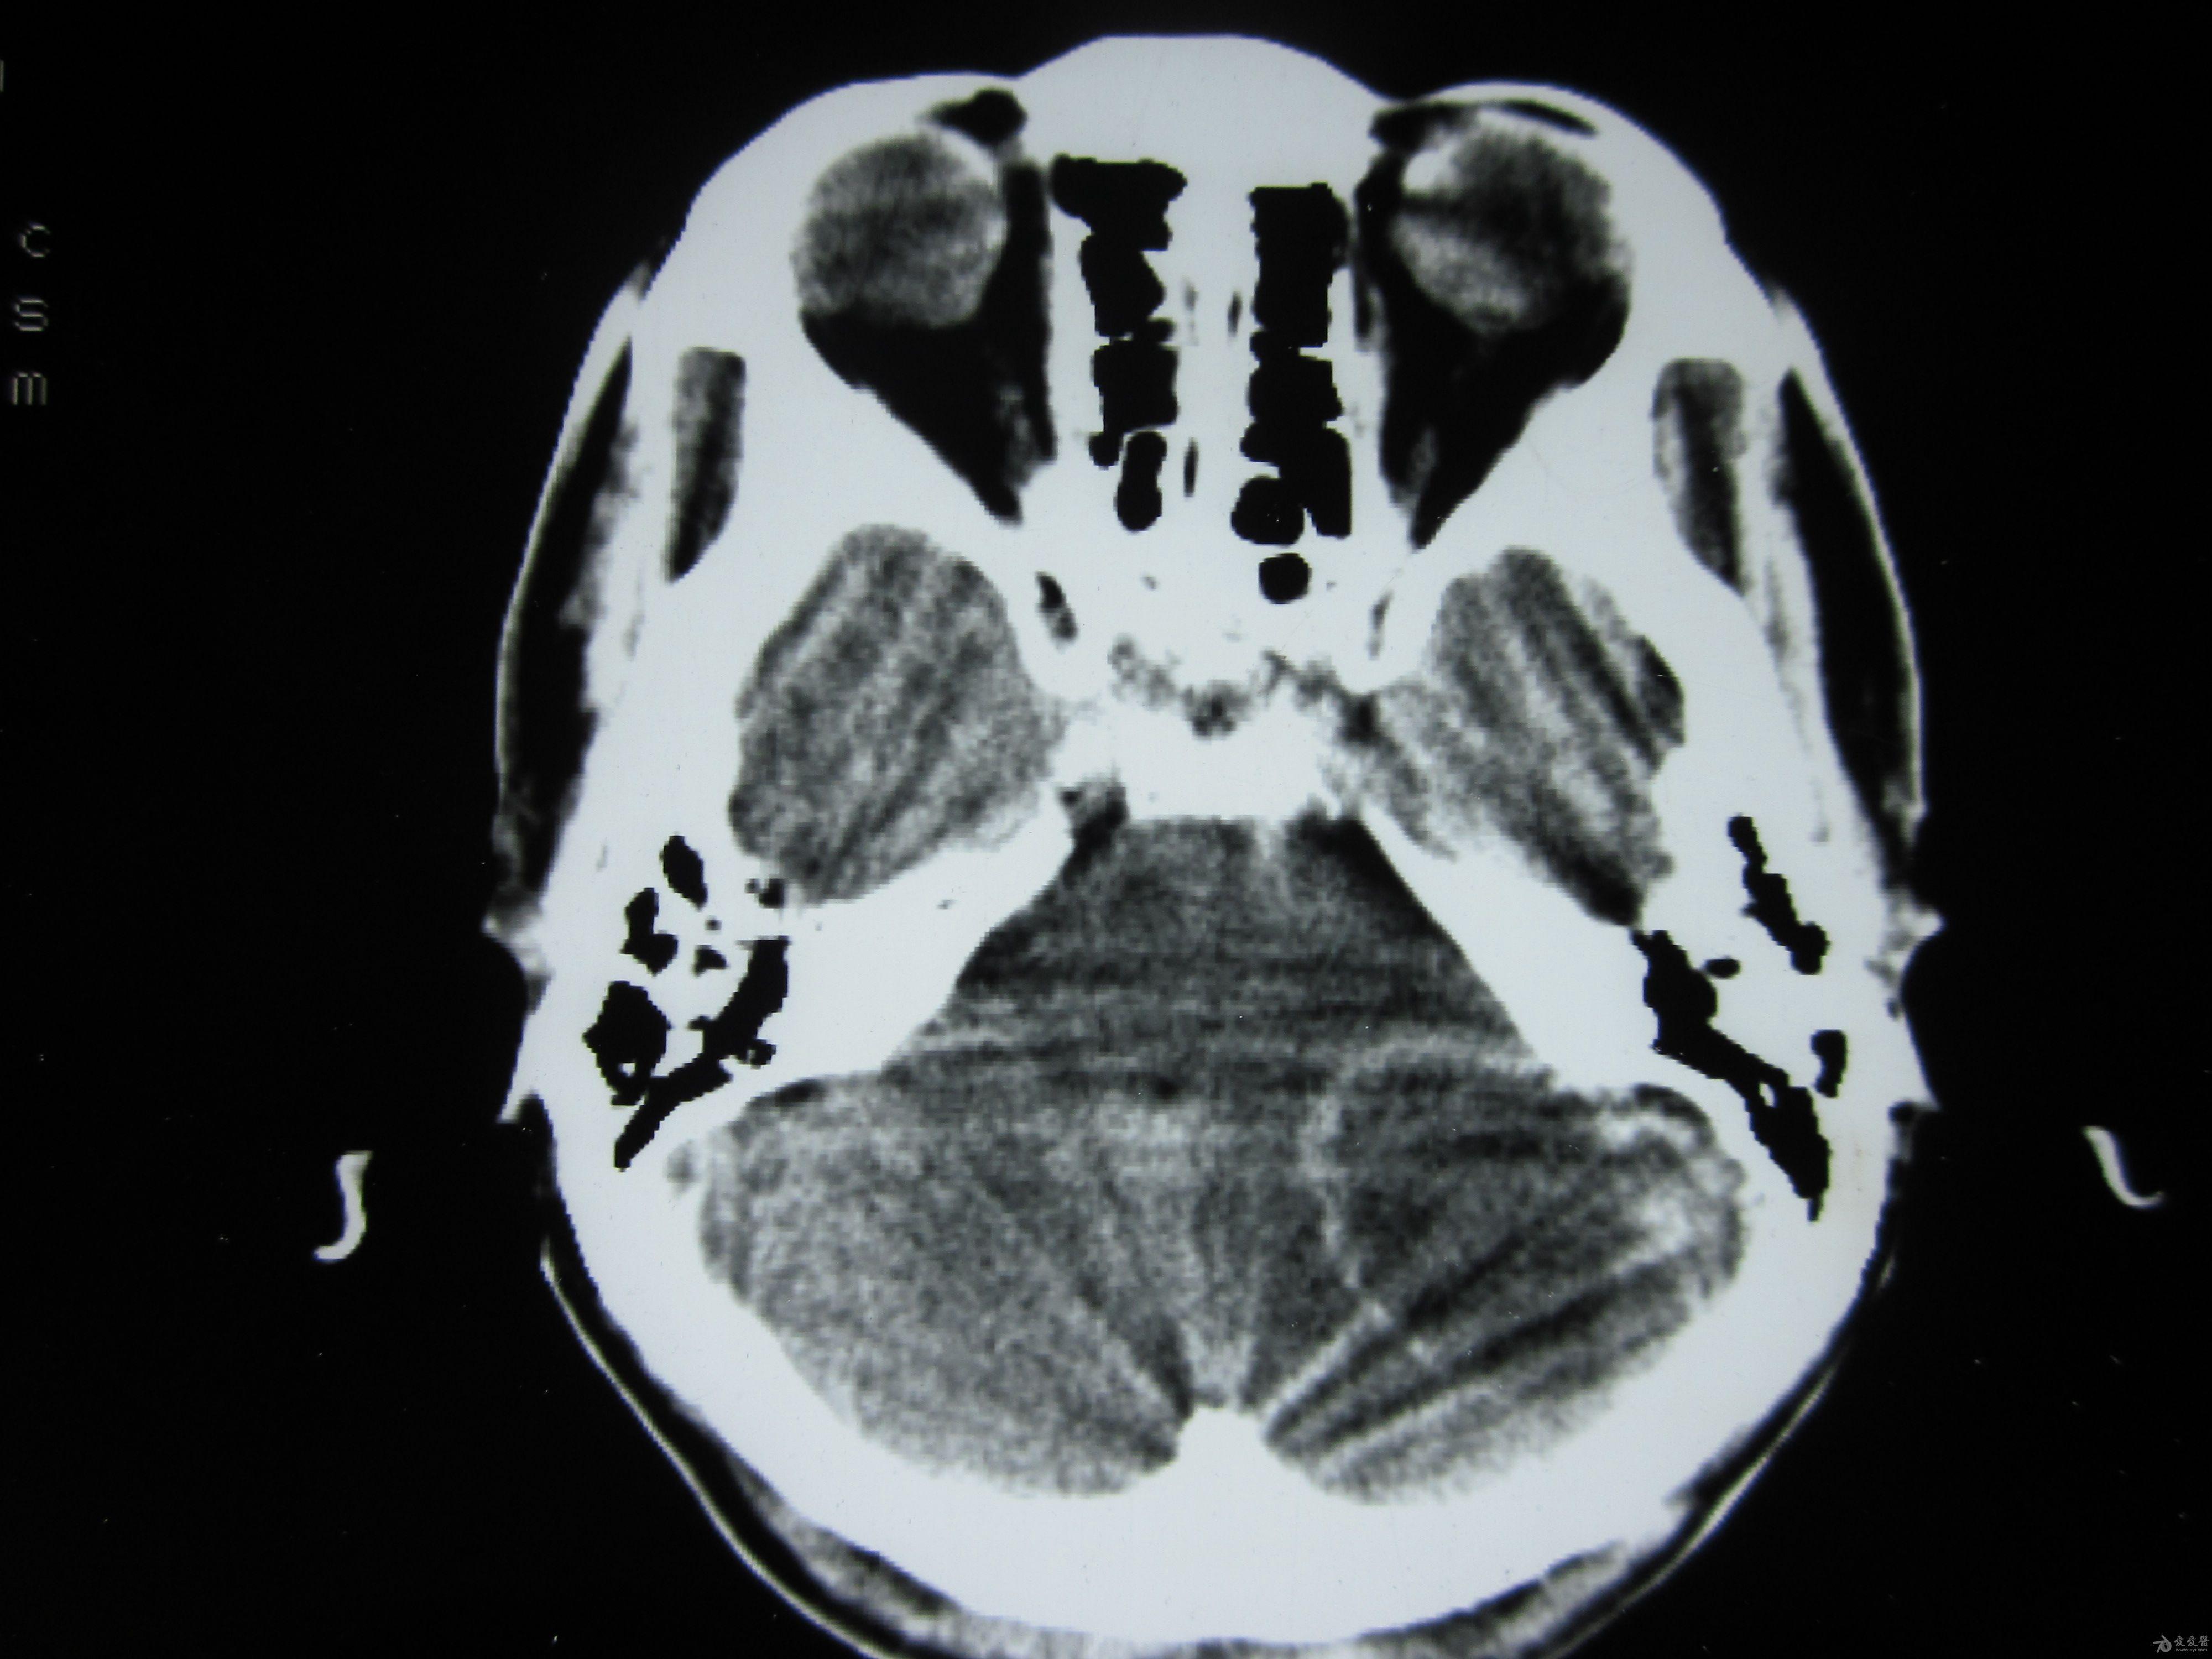

脑转移瘤1.jpg

伽玛刀放射治疗脑转移瘤病案